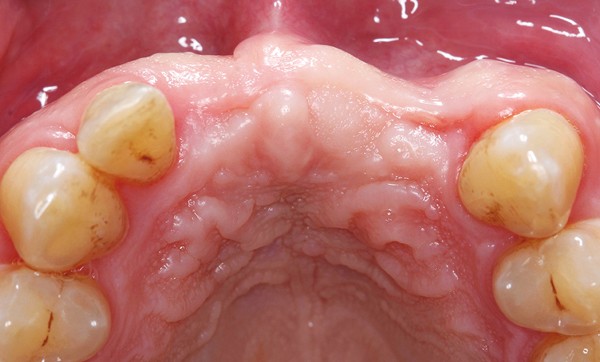

II. Protocole clinique d’utilisation en implantologie